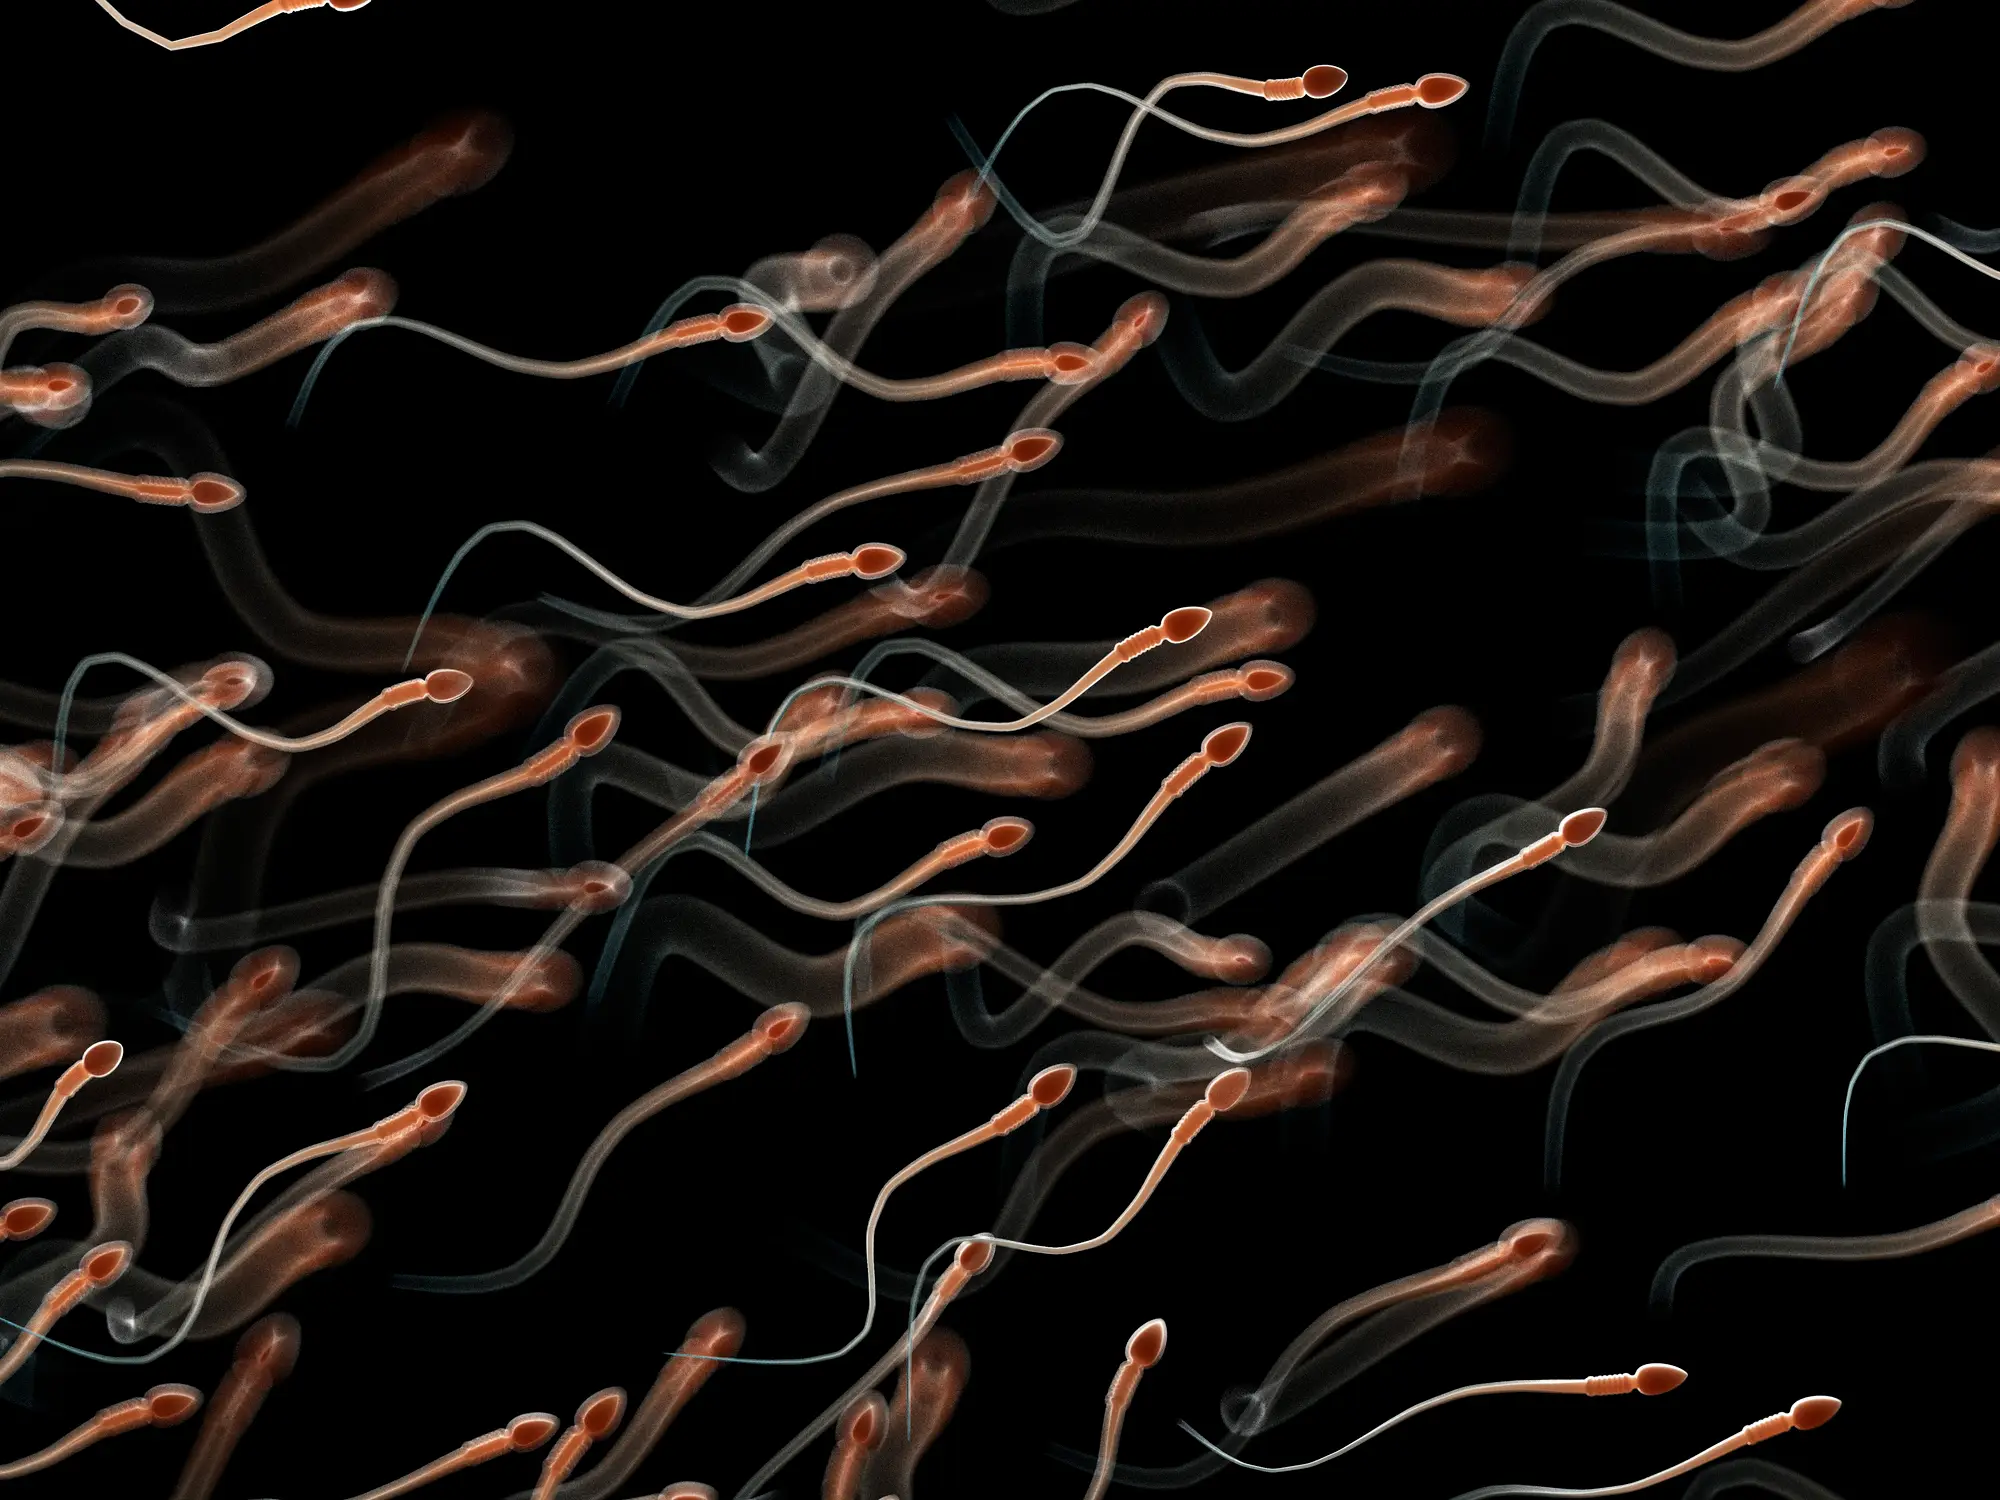

The study looked at the health of sperm (Getty Stock Image)

Researchers looked at key measures like motility (how well sperm move) and viability (how many are alive). Both tended to decline with longer abstinence, while levels of DNA damage increased.